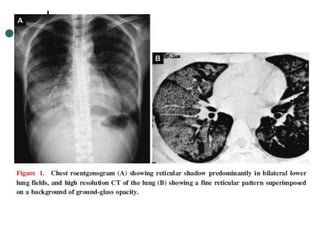

RESPIRATÓRIAS Pneumonite, hipertensão

pulmonar